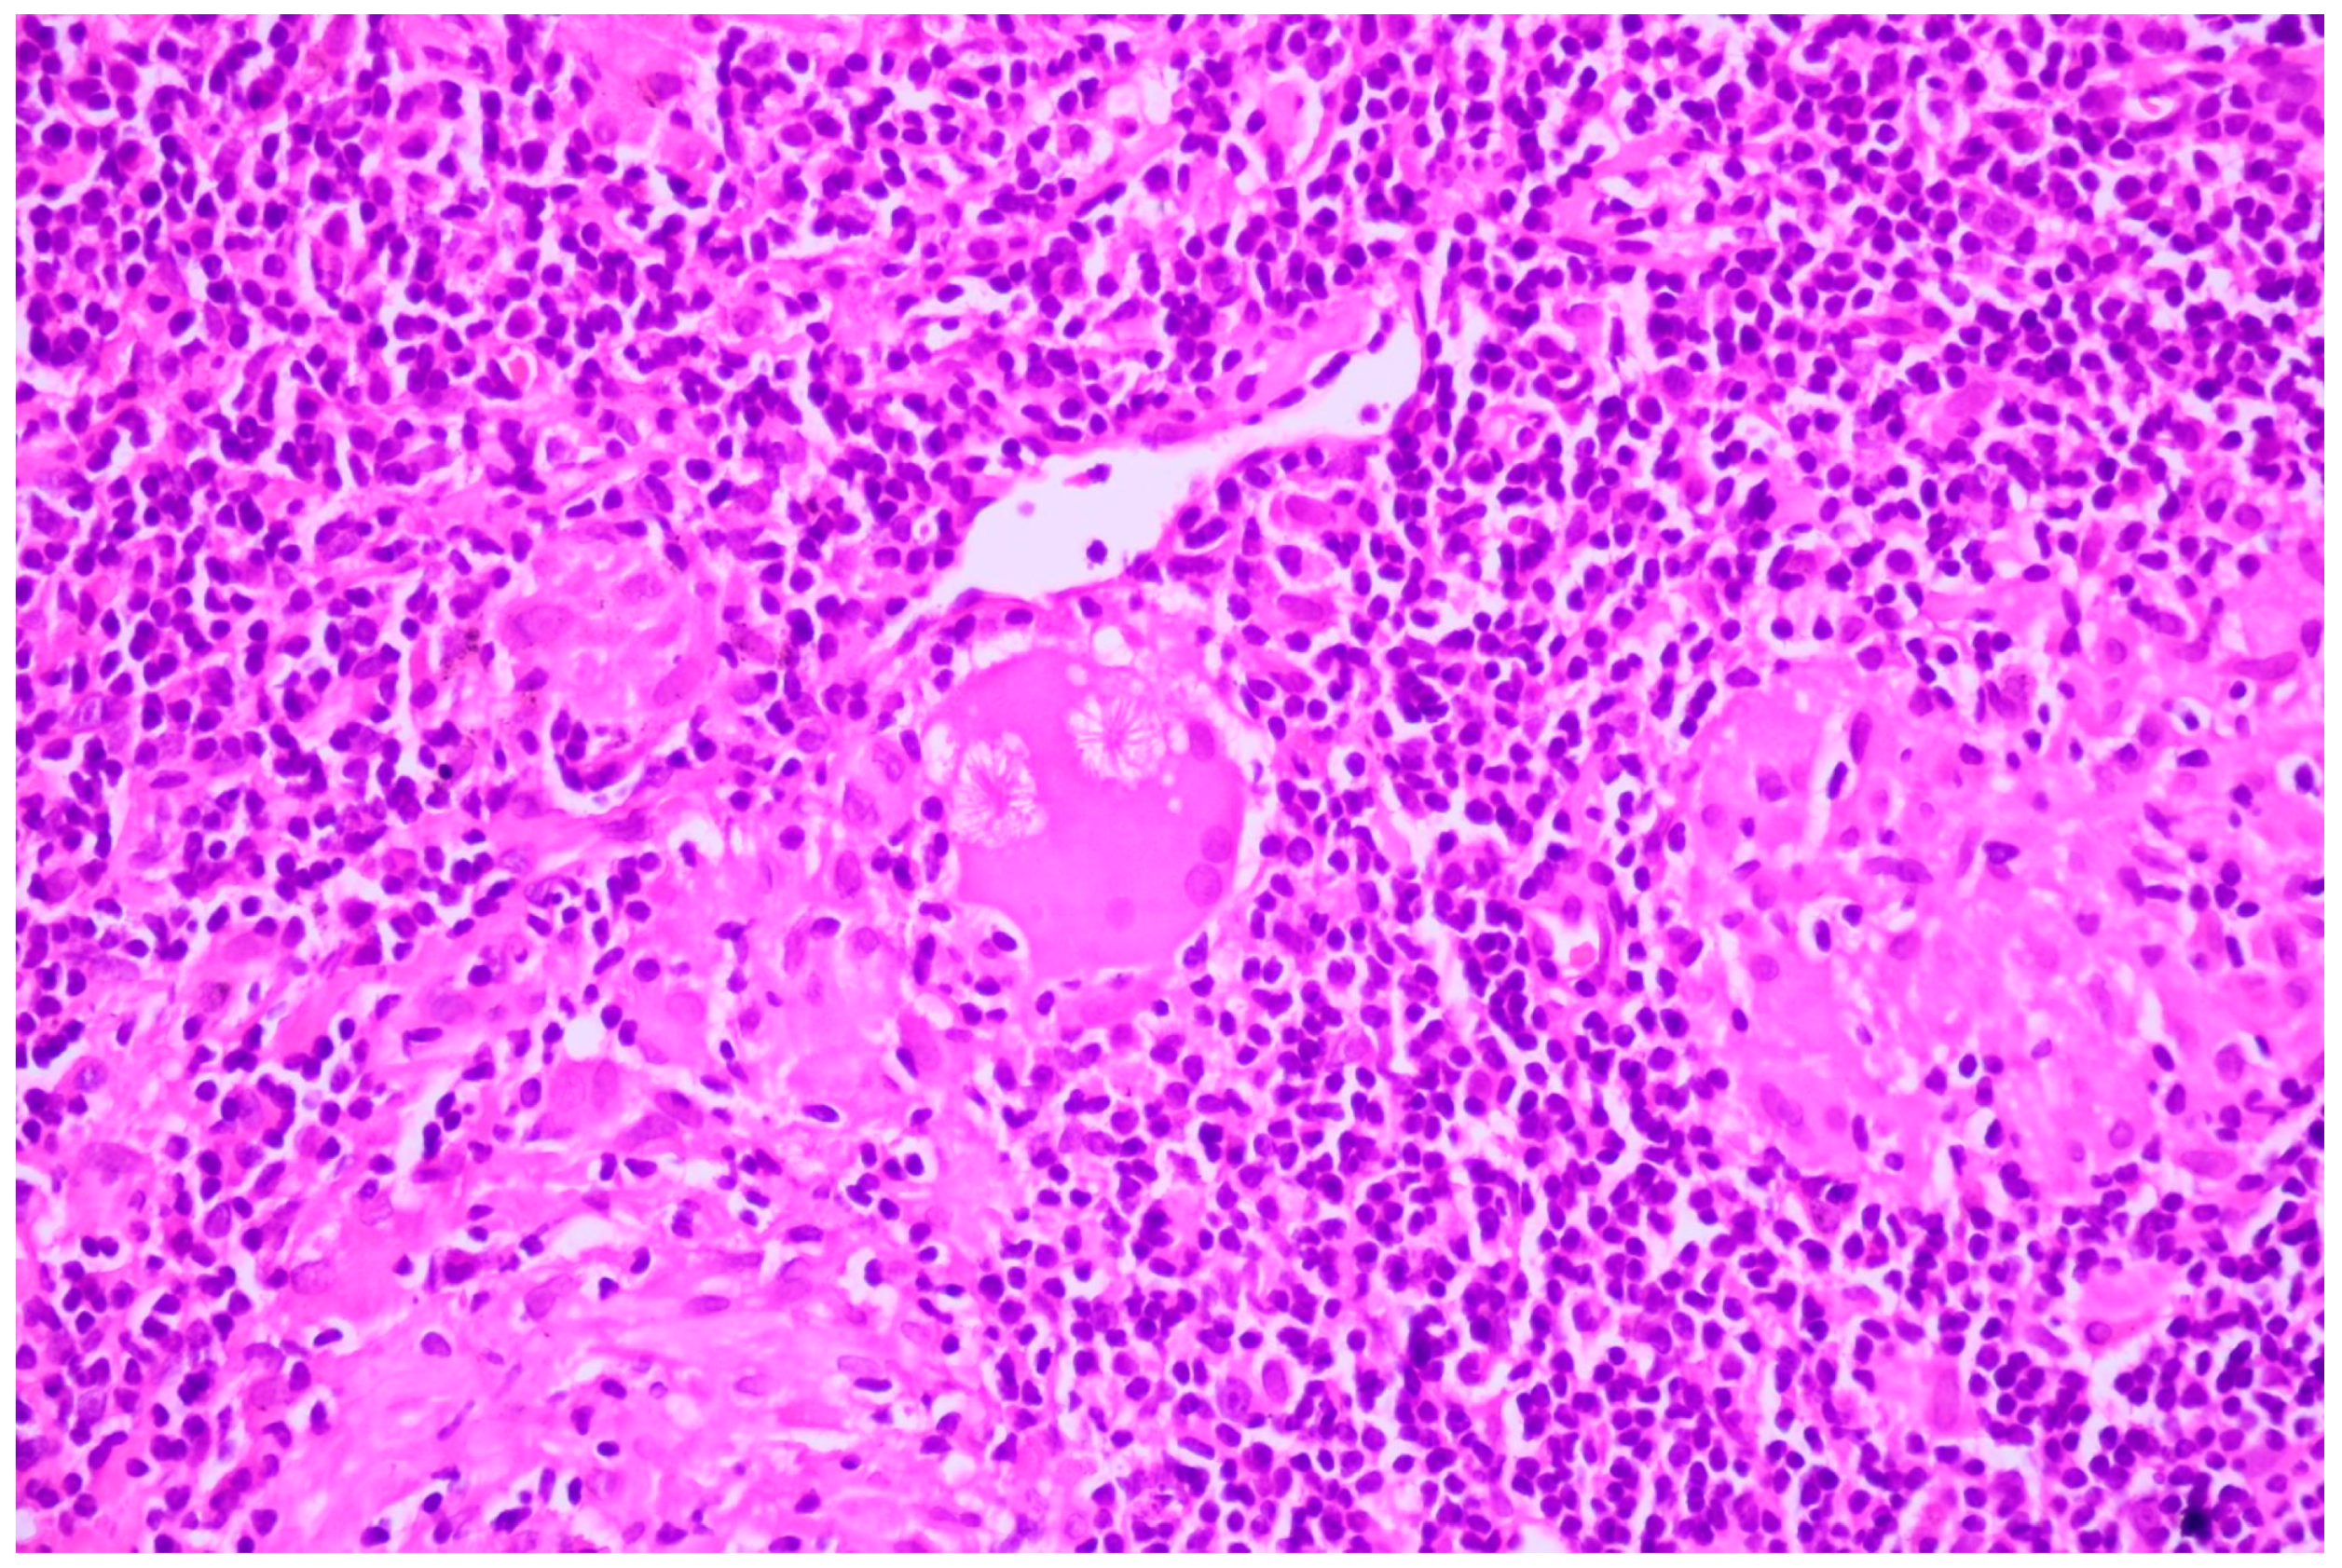

Figure 8. Large-cell neuroendocrine cell carcinoma with abundant tumoral necrosis; HE, 40×.

Two of the specimens with fibronodular lesions were associated with multiple NSCLC tumors of different histopathological subtypes: one case presented with adenocarcinoma (one tumor—Figure 6) and a squamous cell tumor (one tumor—Figure 7) and another case presented with adenocarcinoma (one tumor) and large-cell neuroendocrine tumors (two tumors—Figure 8).